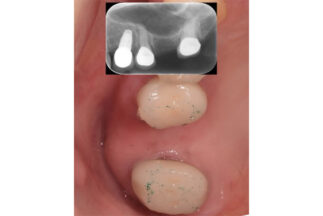

- Before

| 治療内容 | 上顎洞底挙上術(トランスクレスタル、水圧)による単独臼歯修復 |